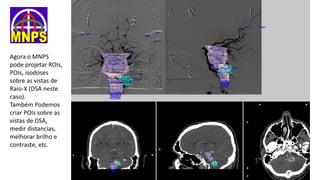

Agora o MNPS

pode projetar ROIs,

POIs, isodoses

sobre as vistas de

Raio-X (DSA neste

caso).

Também Podemos

criar POIs sobre as

vistas de DSA,

medir distancias,

melhorar brilho e

contraste, etc.

Isodoses de 50%

(verde) e 80%

(vermelha)

projetadas sobre

vistas de DAS

registradas no

espaço

estereotáxico.